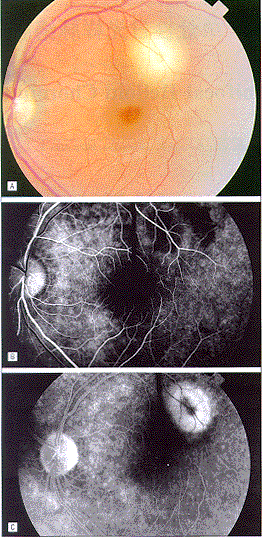

患者视力为OD20/20、OS20/25,眼前节和玻璃体无炎症。眼底检查发现左眼黄斑颞上侧有一黄色、圆形、1.25PD(视乳头直径)的脉络膜炎性病灶,伴视网膜感觉神经层脱离(图1,A),右眼(图1,ABC)正常。荧光血管造影(图1,B和C)显示早期荧光遮蔽,晚期病灶有荧光着染。

图1 病例1、A、眼底照片示黄白色的脉络膜炎性病灶,伴浆液性视网膜脱离。

b、荧光血管造影示早期有荧光遮蔽。C、荧光血管造影示病灶晚期有荧光着染